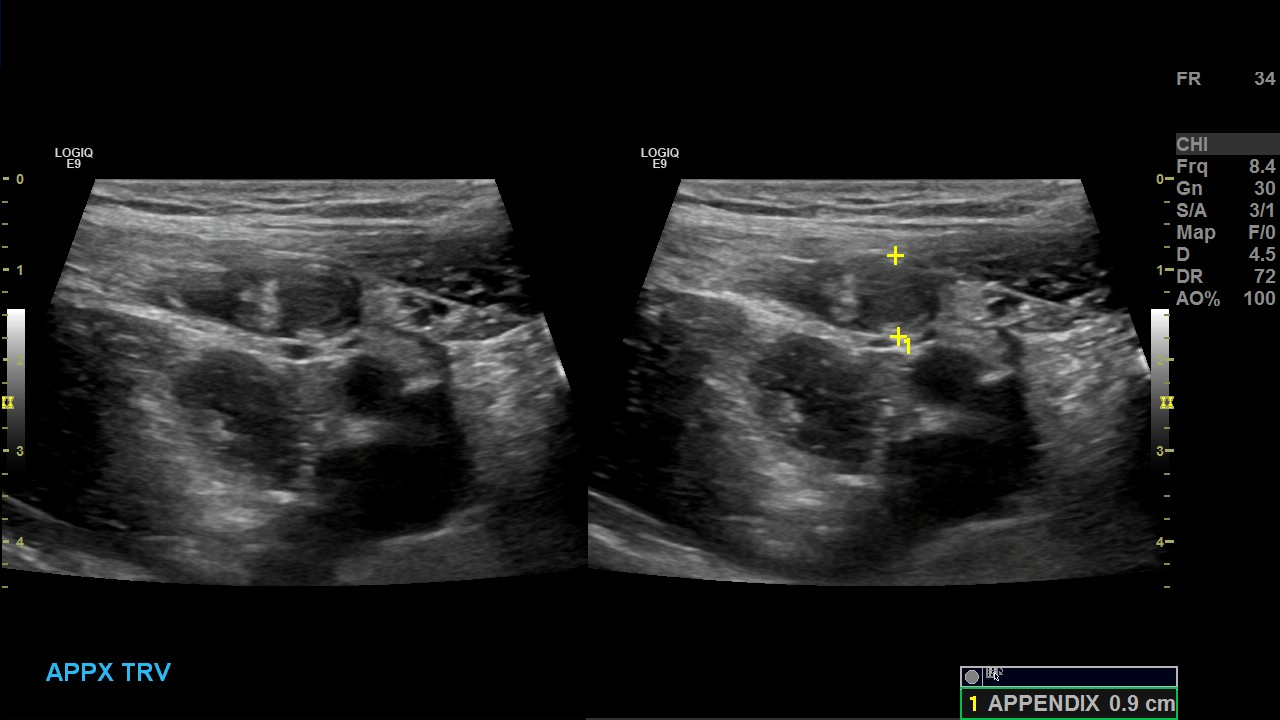

Appendicitis 13

Acute appendicitis @ 1 cm with L2-9mhz and L6-24mhz transducer GE Logiq e10.